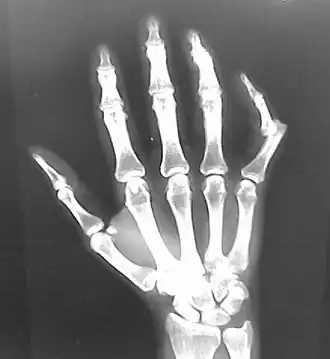

Dislocation of the left index finger -

Radiograph of left index finger dislocation